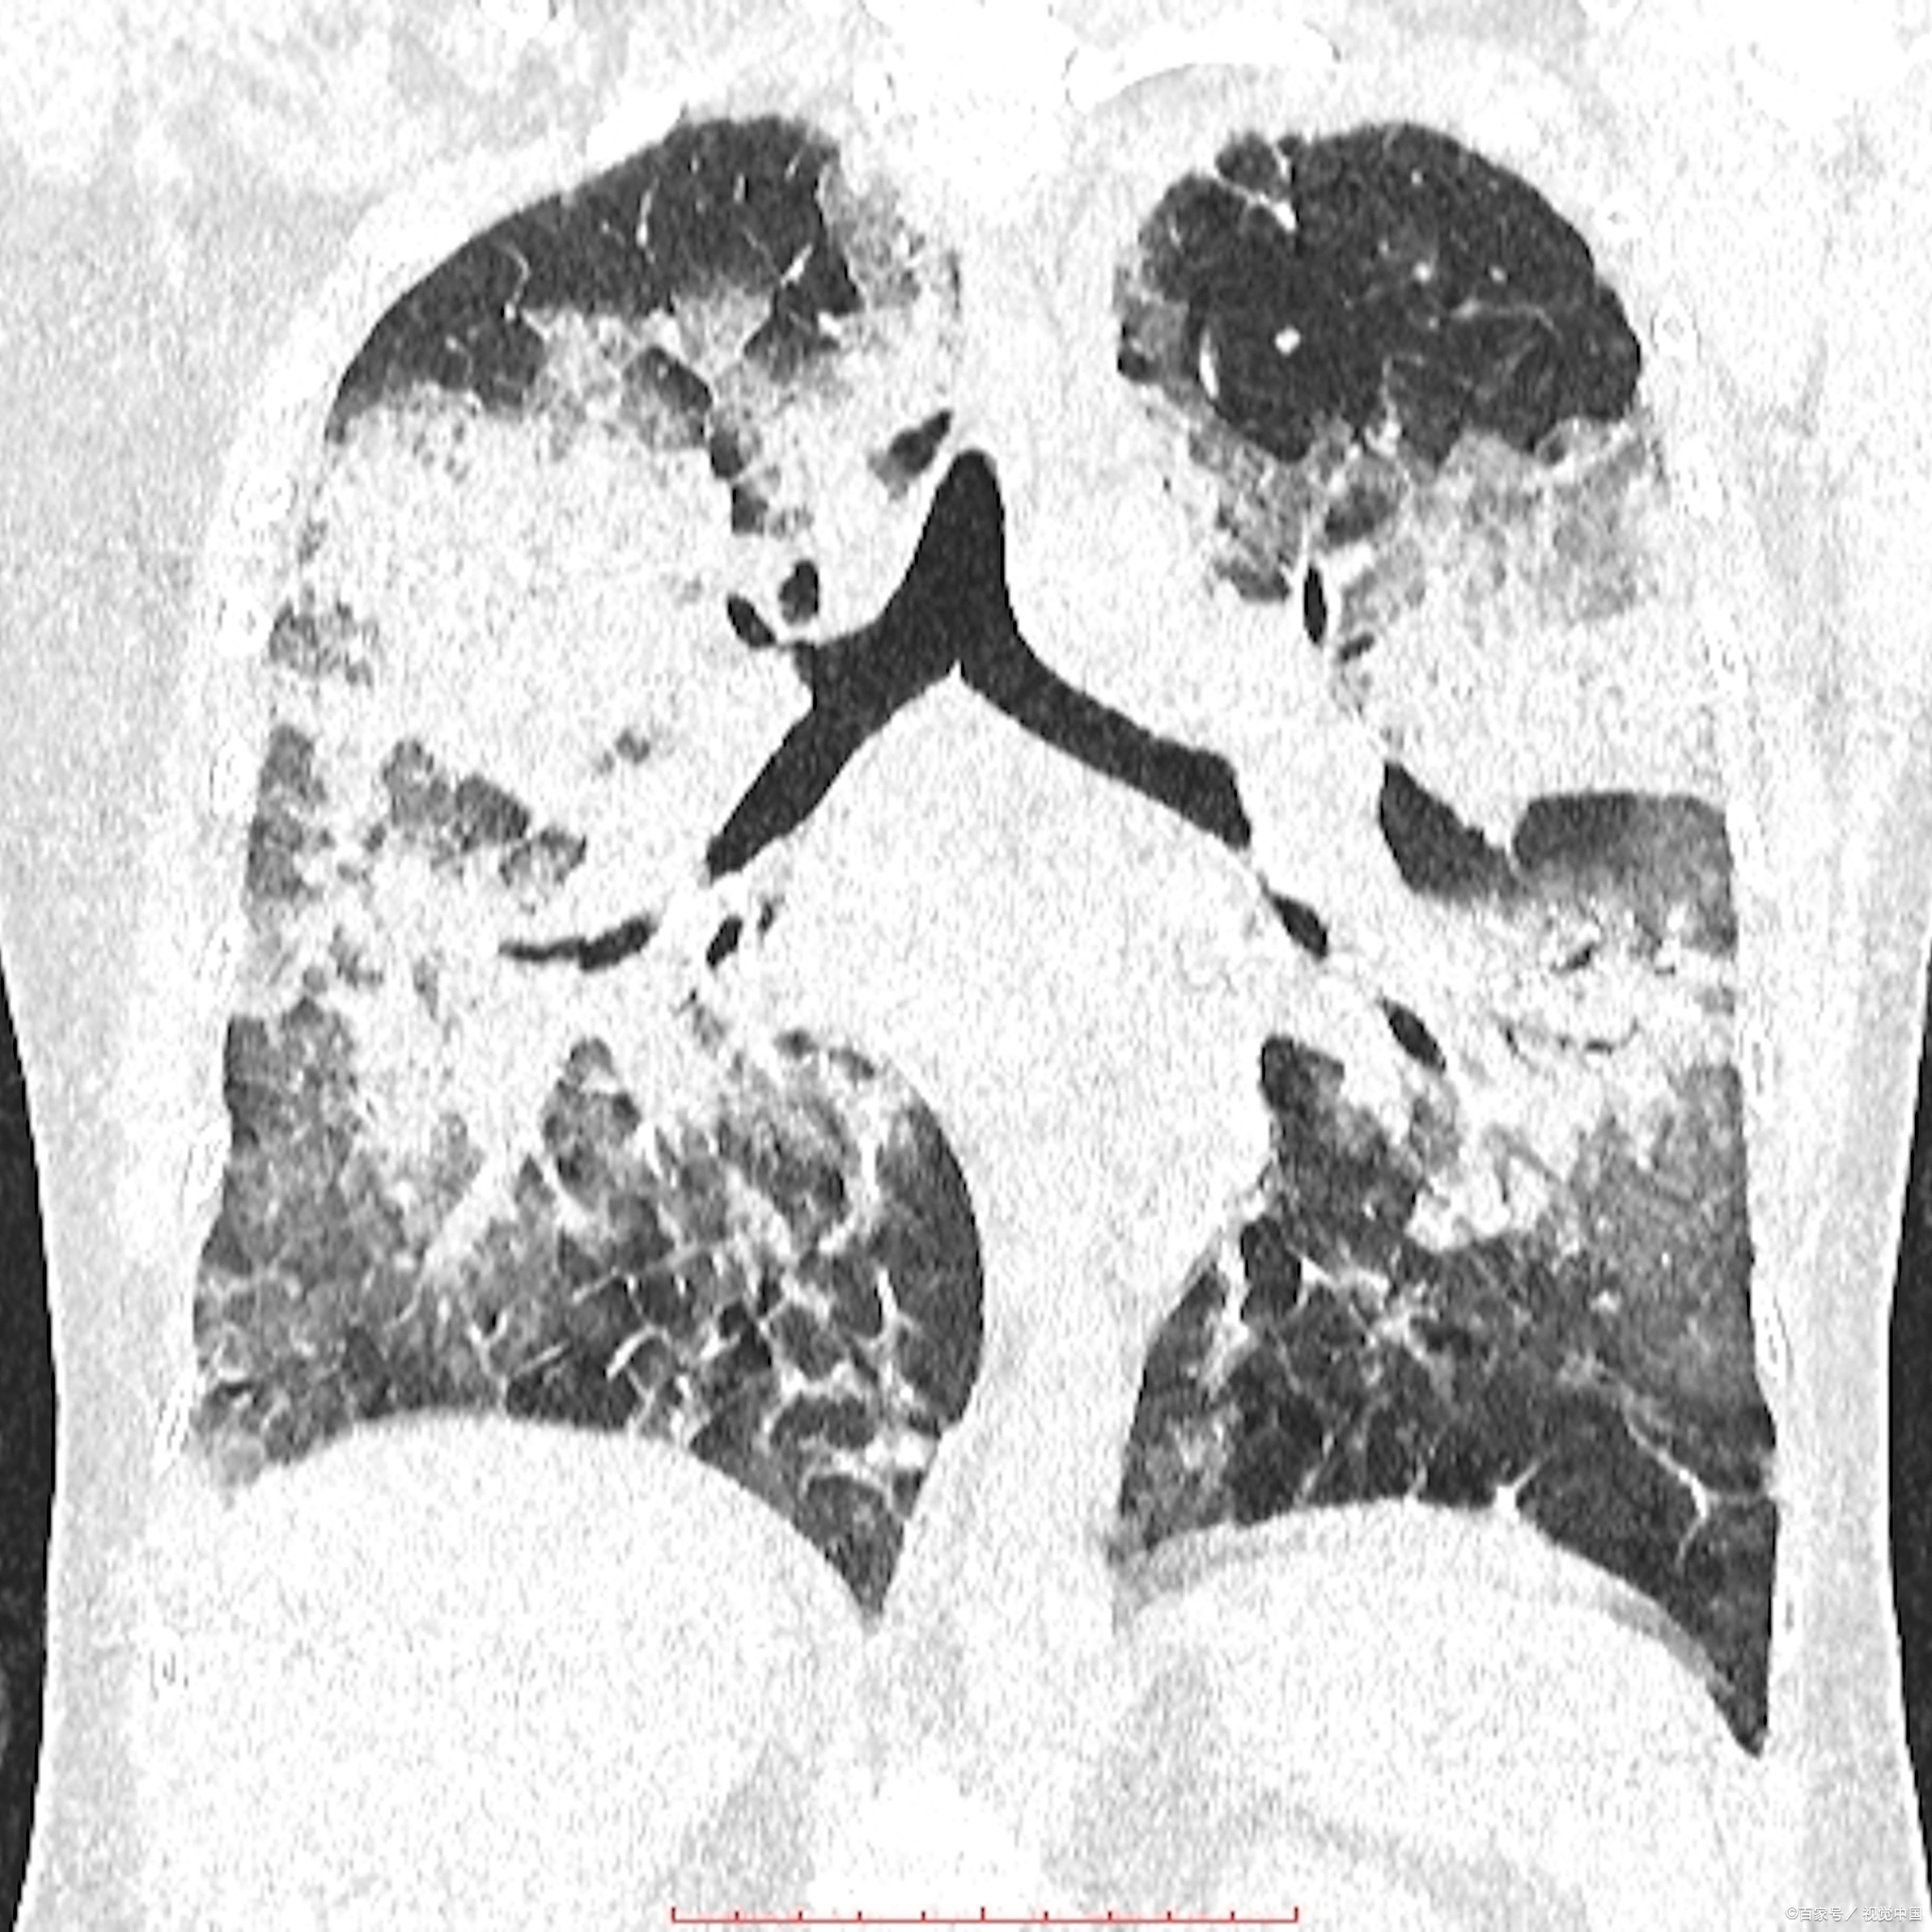

肺纤维化症状根据纤维化类型的不同而有所差异,主要分为局灶性肺组织纤维化和弥漫性肺组织纤维化两种类型,其症状分别如下局灶性肺组织纤维化症状 症状相对轻微,通常继发于肺部的其他疾病,如炎症结核等 临床症状与原发疾病密切相关弥漫性肺组织纤维化症状 起病隐匿起病初期可能无明显。

肺纤维化的症状主要包括以下几点干咳肺纤维化患者常常出现干咳的症状,这是由于肺部纤维化导致肺组织功能受损,刺激咳嗽反射进行性呼吸困难这是肺纤维化最典型的症状之一,表现为呼吸困难逐渐加重,尤其在活动后更为明显随着病情的发展,静息状态下也可能出现呼吸困难杵状指部分患者的手指或脚趾。

肺纤维化症状主要包括以下几点呼吸困难最常见症状轻度肺纤维化时,呼吸困难常在剧烈运动时出现,易被忽视或误诊进行性加重随着肺纤维化进展,即使在静息状态下,也会出现呼吸困难干咳肺纤维化患者常伴有干咳症状,咳嗽可能不伴有痰液或仅有少量痰液乏力患者可能感到全身无力,容易疲劳,这。